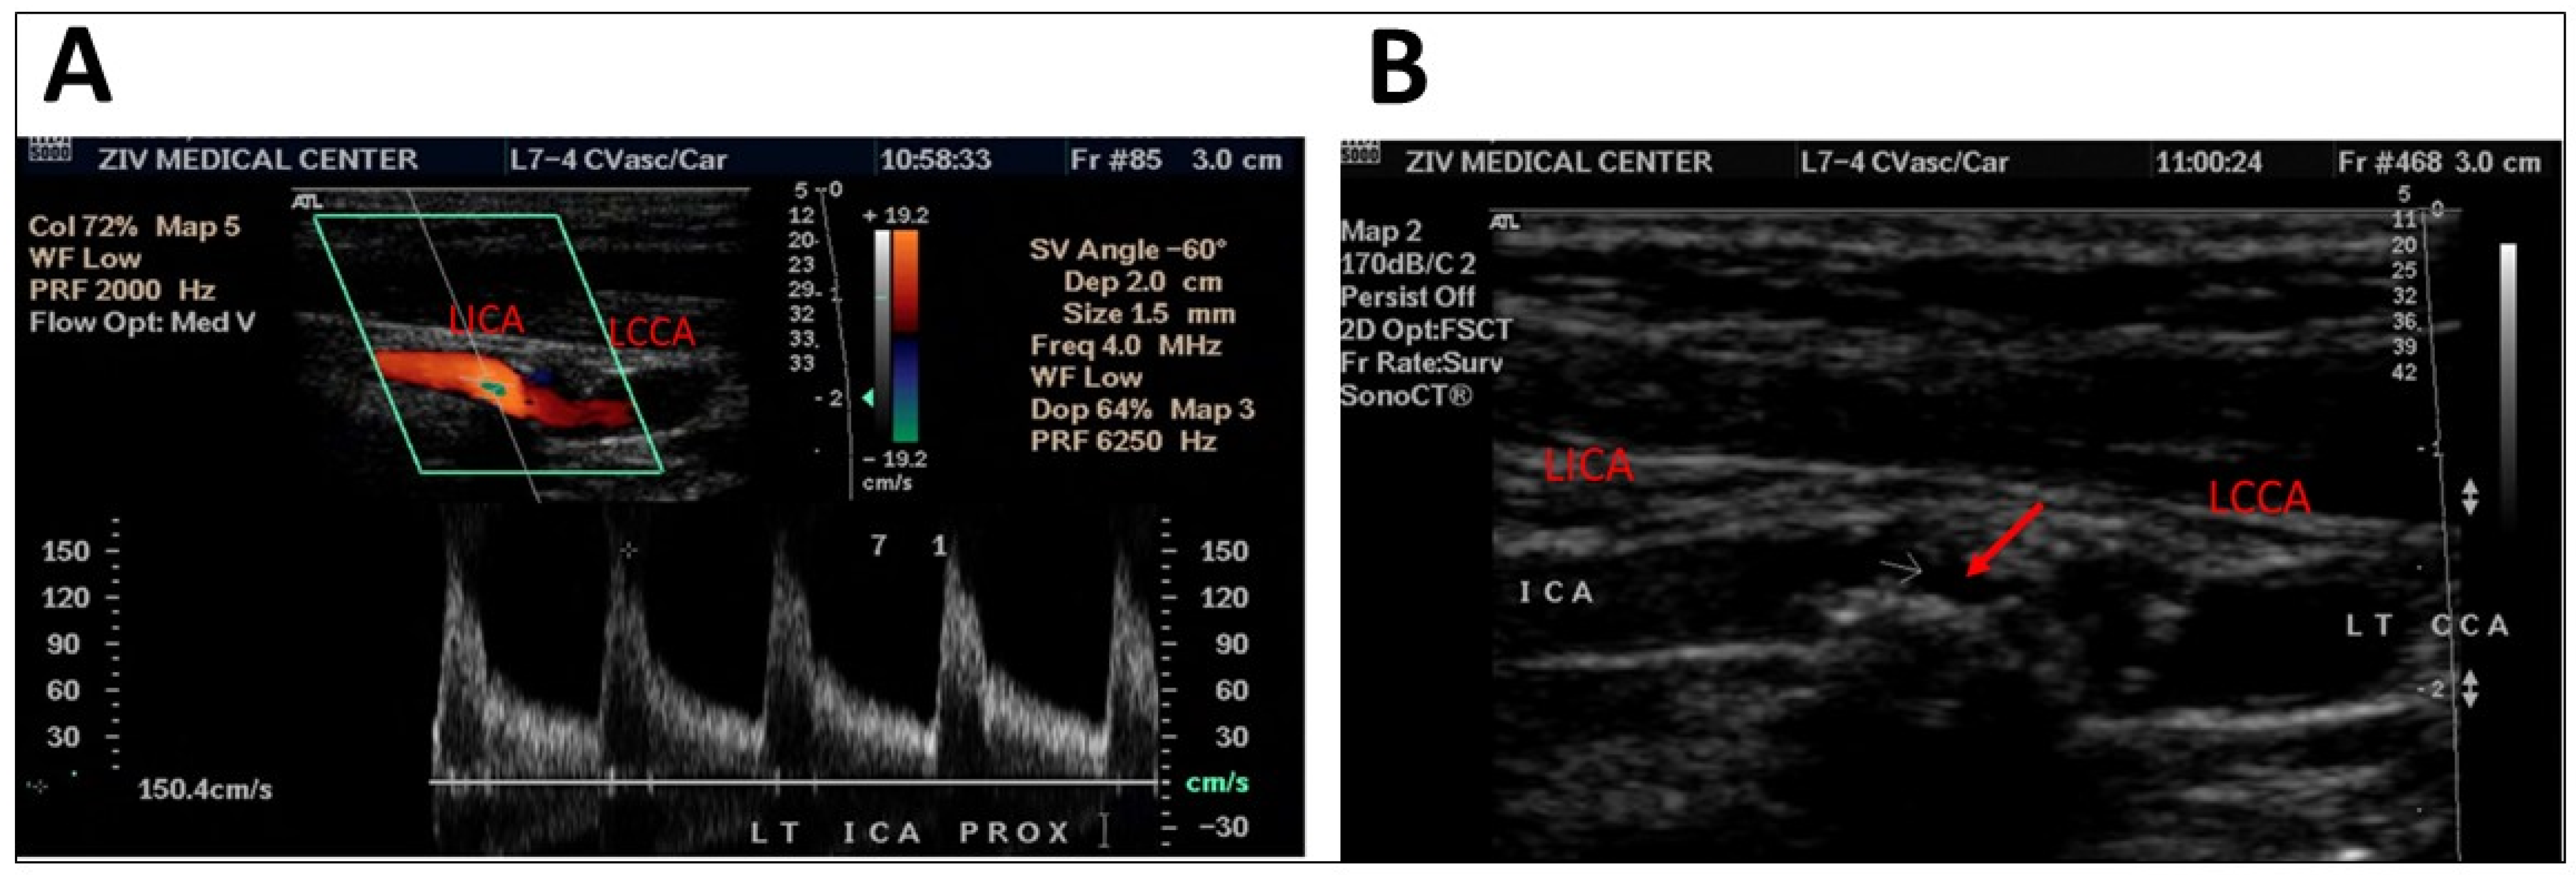

Figure 1.

DUS scan of a patient showing moderate stenosis of 50–70%, as seen by an increase in the flow velocity of the left internal carotid artery (A) and by occlusion site (B, red arrow). LICA = left internal carotid artery, LCCA = left common carotid artery, ICA = internal carotid artery, LT = left, CCA = common carorid artery.